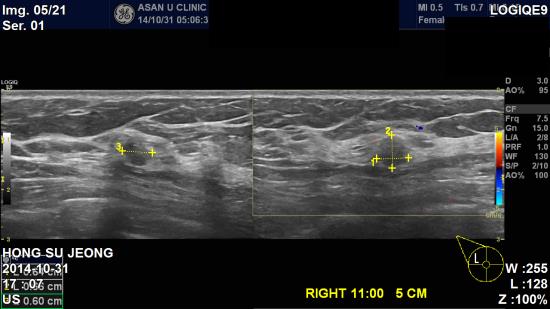

본원에서 유방초음파시행 후, 우측 유방 11시 방향 유두에서 5cm떨어진곳에,

0.66cm 악성의심소견으로 조직검사 시행하여,

침윤성 유관암으로 진단되었습니다.